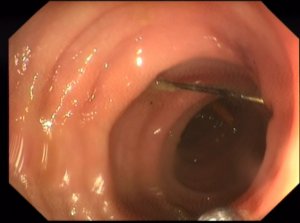

"Швейную иглу раз проглотила женщина, которые любит домашнюю колбасу. В ее куске игла и оказалась. Истыкали ней дыры, когда готовила блюдо. Игла проткнула кишку и осталась торчать. Это случайно обнаружили во время томографии по другой причине. Направили ко мне. Я сразу иглу получил и женщина уехала домой. Даже не знала, что съела острый предмет ", - рассказал Владимир Борисович.